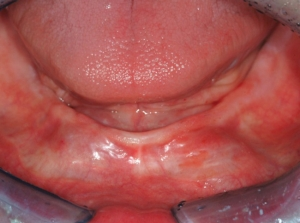

• The physical and mental condition of the patient. If the patient has adequate bone but is physically debilitated, as shown in Fig. 4, I may still decide to use SDIs, since their placement is not as traumatic and time consuming as when placing conventional-diameter implants.

• (Figs. 4-6) Placement of at least four, one piece, small-diameter implants (SDIs) with spherical abutments, two implants at or near each of the canine areas or spread evenly from the canine-to-canine areas if bone presence permits (implant diameter less than or equal to 2.9 mm), and an overdenture.